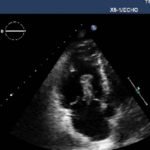

Bedside echocardiogram was performed, which revealed a free-floating thrombus in the right atrium on the sub-xiphoid view as seen in the video. The right atrium is denoted by the blue circle, in which a hyperechoic mobile mass can be seen. This finding was confirmed by an official echocardiogram which shows the thrombus in the right atrium extending through the tricuspid valve, as shown in the second image denoted by the red arrow. Significant right heart strain was also found, with severe pulmonary hypertension and intraventricular septal flattening.